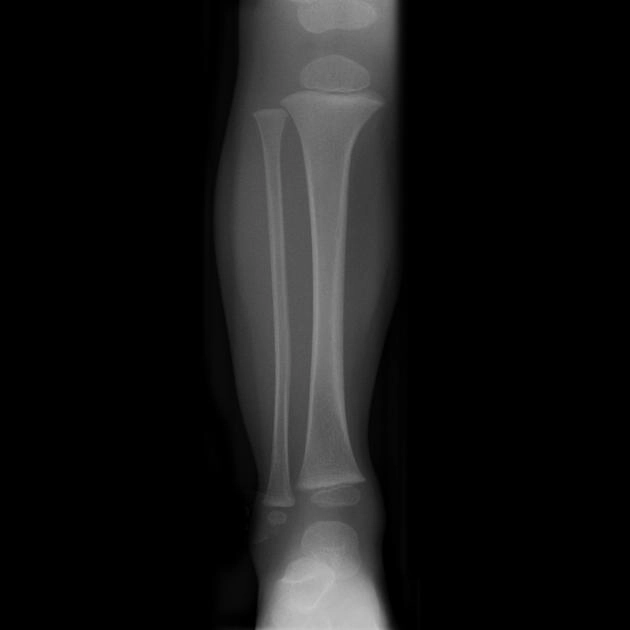

Gãy thân xương chày (Tibial shaft fracture)

16/03/2026